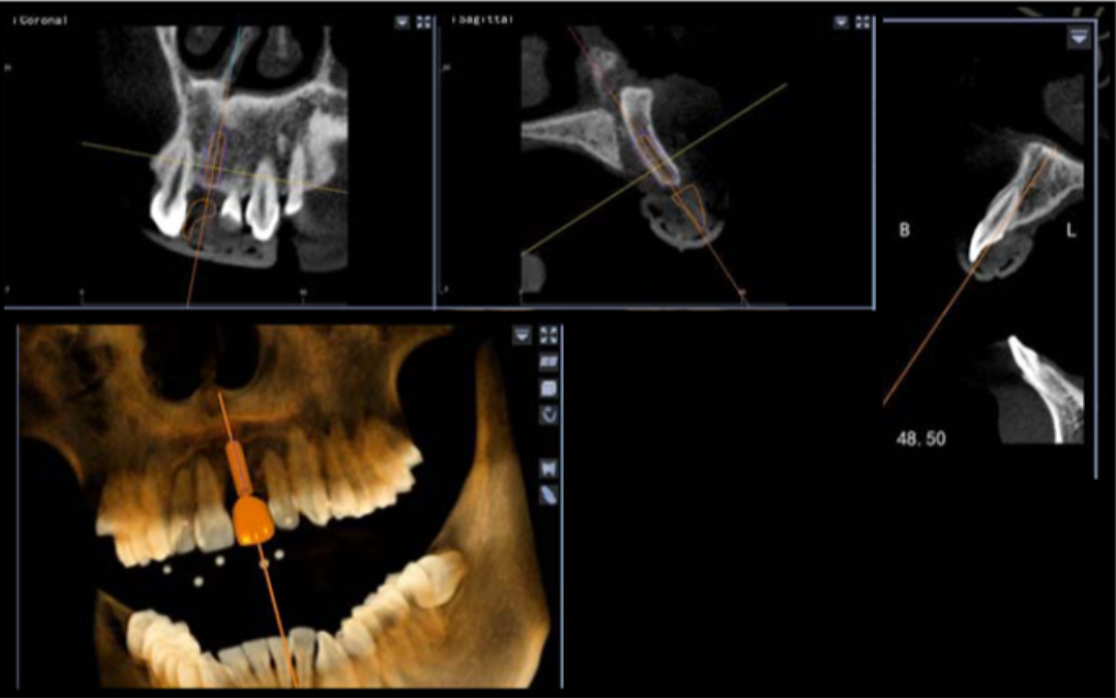

避免骨劈開及切牙管,這是由華西口腔的楊醒眉教授主刀的一次完美的前牙美學(xué)區(qū)數(shù)字化種植手術(shù)的病例!

此病例中主刀醫(yī)生借助迪凱爾數(shù)字化口腔種植手術(shù)導(dǎo)航系統(tǒng),精確的控制每鉆的定點精度和角度,保證了每次制備定點誤差小于0.4mm,角度偏差不大于3.5°,極大的保證了種植體按照種植前的手術(shù)設(shè)計就位。